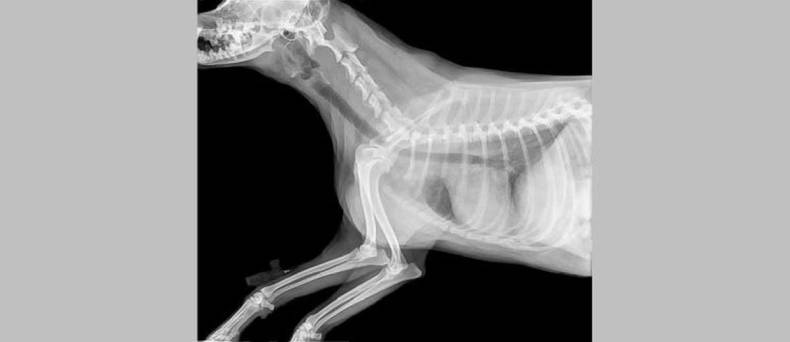

Een zeer veel gebruikt diagnostisch hulpmiddel van de dierenarts is de radiografie, RX of Röntgenfoto. Een radiografie toestel genereert X-stralen die door het lichaam of lichaamsdeel van de patiënt worden geleid. Deze stralen gaan gemakkelijk door lucht en door water, maar worden gedeeltelijk tegengehouden door dichtere structuren, zoals de organen en (vooral) beenderen.

Onder het dier wordt een soort negatief film gelegd die de stralen opvangt die niet onderweg zijn tegengehouden in het lichaam van de patiënt. Na ontwikkeling komen we dan tot een foto die een beeld geeft van het inwendige van het dier.

Radiografieën kunnen zeer goed harde weefsels, zoals botten, in beeld brengen. Voor het beoordelen van de organen is de techniek bruikbaar, maar minder geschikt. De techniek is relatief goedkoop in vergelijking met andere beeldvormende technieken en al lang in gebruik.